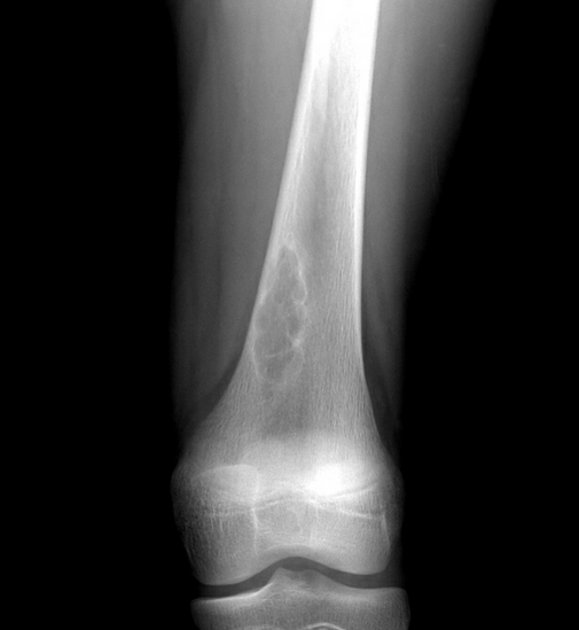

Diagnosis?

What is it?

Non-ossifying fibroma. (if smaller called fibrous cortical defect, aka MFD)

The most common of benign fibrous bone lesions, common in children and adolescents (peak incidence 10-15 years). They are usually not seen beyond the age of 30, as they spontaneously heal being gradually filled in by bone.